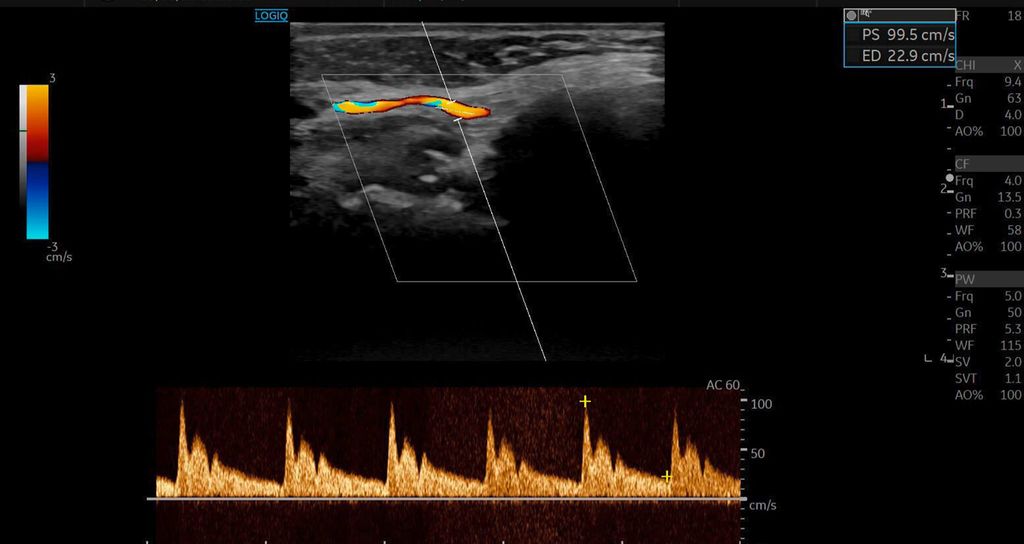

Die Duplexsonografie ergab folgende Befunde (Abb. 5 und Abb. 6):

-

Der Durchmesser der A. angularis und A. facialis hatte sich nahezu verdoppelt.

Die systolische Spitzengeschwindigkeit (PSV) stieg von 20cm/s auf über 100cm/s.

Die enddiastolische Geschwindigkeit (EDV) betrug nun 20cm/s, was auf eine periphere Vasodilatation und eine Wiederherstellung der Makrozirkulation hindeutete (Abb. 7).